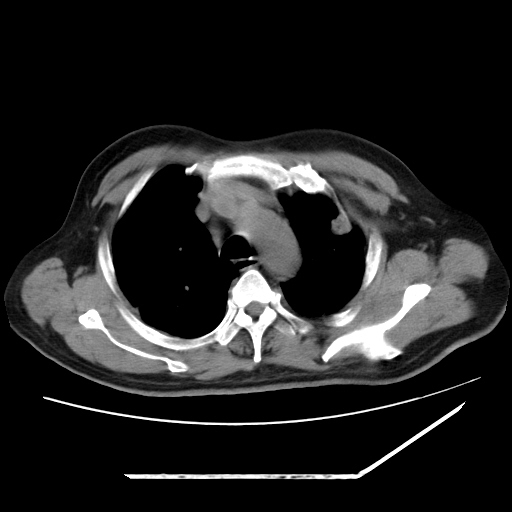

男,57,畏寒,发热

两肺野多发大小不一高密度灶,纵膈内见肿大淋巴结,要考虑转移瘤可能。双侧胸腔少量积液。

双肺多发结节样病灶,部分内见透光区,纵隔内见淋巴结肿大。结核临床如有畏寒,高热,白细胞增高首先考虑迁徙性肺脓肿(多是金黄色葡萄球菌感染)。

注意除外转移瘤。

1)考虑两肺感染性病变(金黄色葡萄球菌肺炎?);建议抗炎治疗后复查排除其他。2)双侧少量胸腔积液。